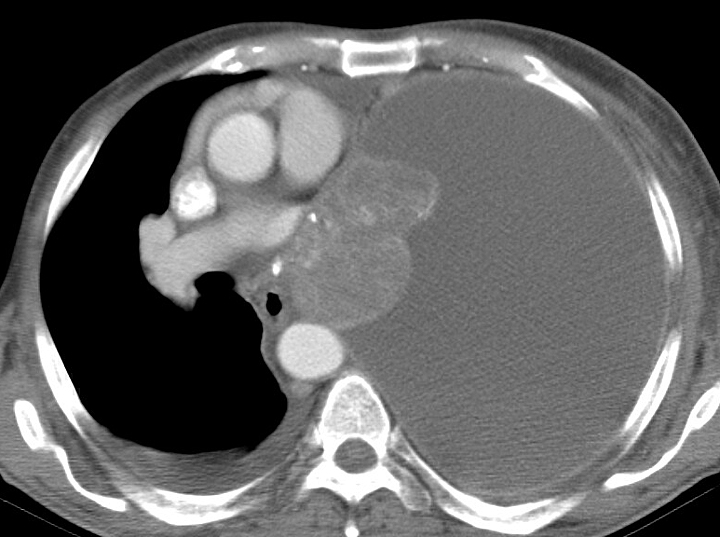

Pleural

huge effusion CT

Date: 09/24/2006

Full size: 720x537